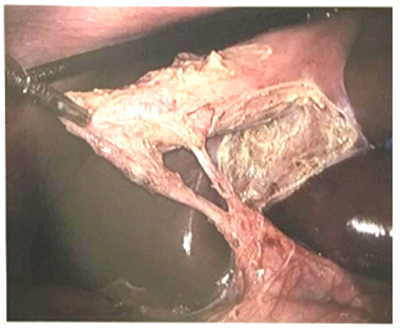

Recomendamos como primer paso la búsqueda del surco de Rouviere, ya sea en forma de cicatriz, hendidura o surco, para iniciar la disección por arriba de este surco, evitando cualquier disección por debajo de este punto de referencia, para eliminar cualquier peligro de LVB 22 (figura 3). La mano del cirujano, a través de T3, puede manipular el cuello de la VB para exponer la cara anterior (medial) y posterior (lateral), según sea necesario. Si la VB se encuentra a tensión, se recomienda descomprimirla con un dispositivo de aspiración con aguja, para evitar perforaciones con derrames de bilis y cálculos biliares. Si hay adherencias, se eliminan con tracción o con corte frío, evitando el uso de energía cerca del duodeno y de la vía biliar principal.